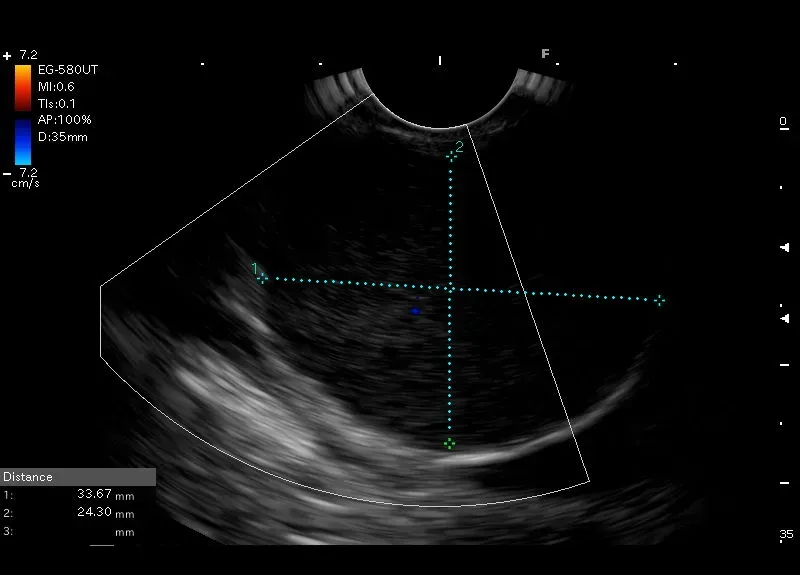

Wywodząca się z muscularis propriae ściany żołądka, owalna zmiana wielkości 34/24 mm, z drobnymi bezechowymi przestrzeniami oraz widocznymi w badaniu doppler miejscami przepływu naczyniowego - w pierwszej kolejności obraz odpowiada GIST.